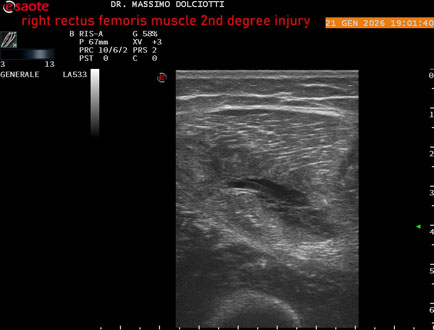

Data inserimento: 23/01/2026

Ecografia del: 21/01/2025

Strumento: Esaote MyLab Eight

Sonda: Lineare Multifrequenza 3-13 MHz

Età Paziente: M 23 anni

Motivazione dell'esame: dolore al terzo prossimale della coscia destra da tre giornii.

Commento all'esame: le immagini ed il video documentano, al terzo prossimale del muscolo retto femorale destro, area disomogenea, ipoecogena, delle dimensioni di 35 mm per uno spessore di 18 mm, misura ottenuta per asse corto o trasversale, e di 71 mm x 20 mm, misura ottenuta per asse lungo o longitudinale, da ricondurre a lesione muscolare di 2° grado con modica raccolta sieroematica intramuscolare.

Conclusioni: lesione di 2° grado del muscolo retto femorale destro (2nd degree injury of the right rectus femoris muscle).